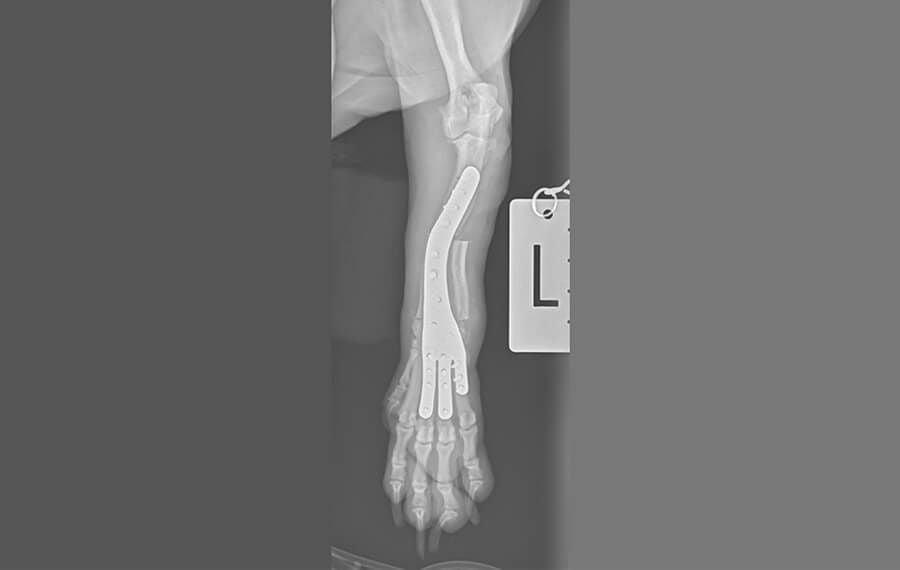

Growth Deformities: Precision Correction with 3D Technology

Growth plate injuries in young, developing pets can lead to significant limb deformities. When one part of a bone stops growing while the rest continues, the limb can bow, twist, or shorten (often referred to as Angular Limb Deformities).

At VSOS, we don't rely on "eyeballing" these complex corrections. We utilise advanced 3D Surgical Planning and Patient-Specific Guides to ensure that a crooked limb is straightened with mathematical precision.

Once the virtual plan is perfected, we 3D-print a custom surgical guide system designed specifically for your pet's unique bone shape. These guides act as a "GPS" for the surgeon's tools.

Translation of the Plan: The guides fit onto the bone in only one exact position. They feature pre-designed slots and holes that dictate the exact angle of the bone cut and the precise trajectory of every drill hole.

Eliminating Human Error: By using these guides, the angular corrections we planned on the computer are translated perfectly to the patient in the theatre. This ensures the limb is straightened exactly as intended, down to the millimetre.